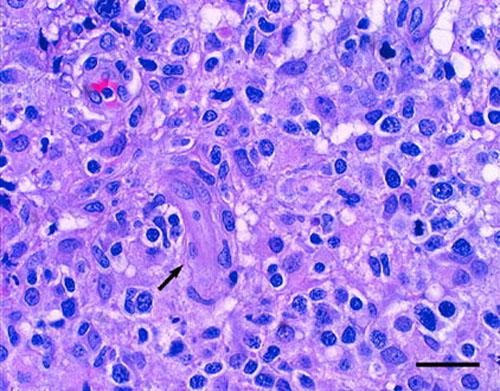

Enfin, un examen histopathologique des lésions a été demandé sur les derniers prélèvements. Les images observées étaient compatibles, dans la mesure ou le caractère stérile était démontré, avec un histiocytose réactionnelle (photo 4 et 5).

histiocytose-cutanee5

Photo 5 : vue rapprochée de la photo 4, infiltrat inflammatoire granulomateux

centré au tour d’un vaisseau sanguin (flèche) (HE, x 1000)